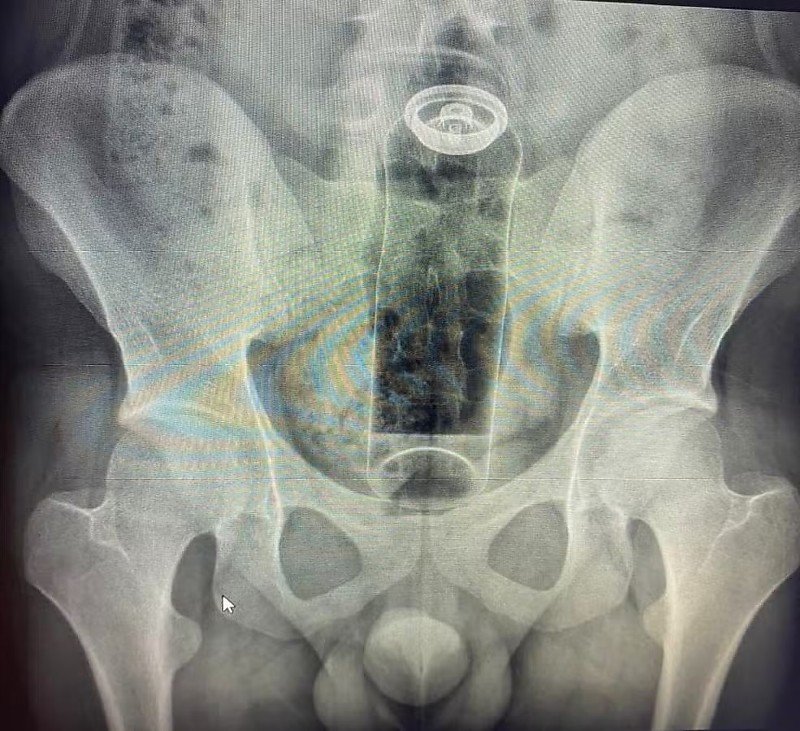

De acordo com o médico Daniel Brosco, cirurgião coloproctologista, o paciente tinha 19 anos e contou que colocou o desodorante no ânus durante uma “brincadeira” sexual. A embalagem, porém, acabou subindo para o reto e não conseguiu ser retirada em casa.

“A fantasia não é um problema. O problema é não usar objetos específicos para isso. Imagina se o conteúdo da embalagem vaza ou se o objeto sobe de uma forma que exige cirurgia para retirar? Já tive pacientes que acabaram com infecções graves e morreram”, alertou Daniel Brosco, cirurgião coloproctologista.